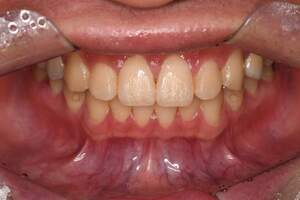

歯石除去

治療前

治療後

| 年齢 | 25歳・男性 |

| 主訴 | 歯石をとりたい・検診 |

| 治療内容 | 各種検査・歯石除去 |

| 治療期間 | 60分 |

| 費用 | 初診料3,000〜4,000円前後 +歯石除去約1,000円 |

| リスク・副作用 | ・処置後に歯がしみることがあります。 ・歯と歯の間に隙間ができるので、息が漏れ発音しにくいと感じることがあります。 ・歯ぐきの炎症が軽減すると歯ぐきが引き締まり、歯が長く見えることがあります。 |

| 担当者所見 | 前歯の裏側にすぐに歯石が溜まってしまいザラザラして気になるとご相談いただいたので適切な歯ブラシの当て方とフロスの通し方をお伝えさせて頂きました。 |